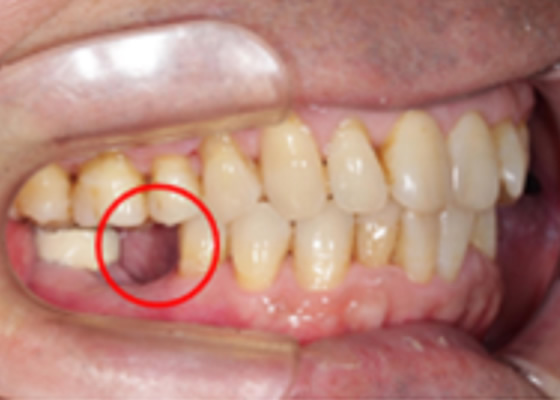

治療内容:奥歯が噛めない、歯を白くしたいという主訴に対してインプラント治療、セラミック治療を行った症例。

治療費:¥220,000~/1本×2 ハイブリッド冠¥55,000×3 診断料:¥22,000

副作用・リスク:インプラントオペによる一時的な炎症・出血や顔面の内出血、治療終了後のメンテナンス不足による歯周病やインププラント周囲炎、歯ぎしりや過剰な噛み締めによるセラミックスの破折。